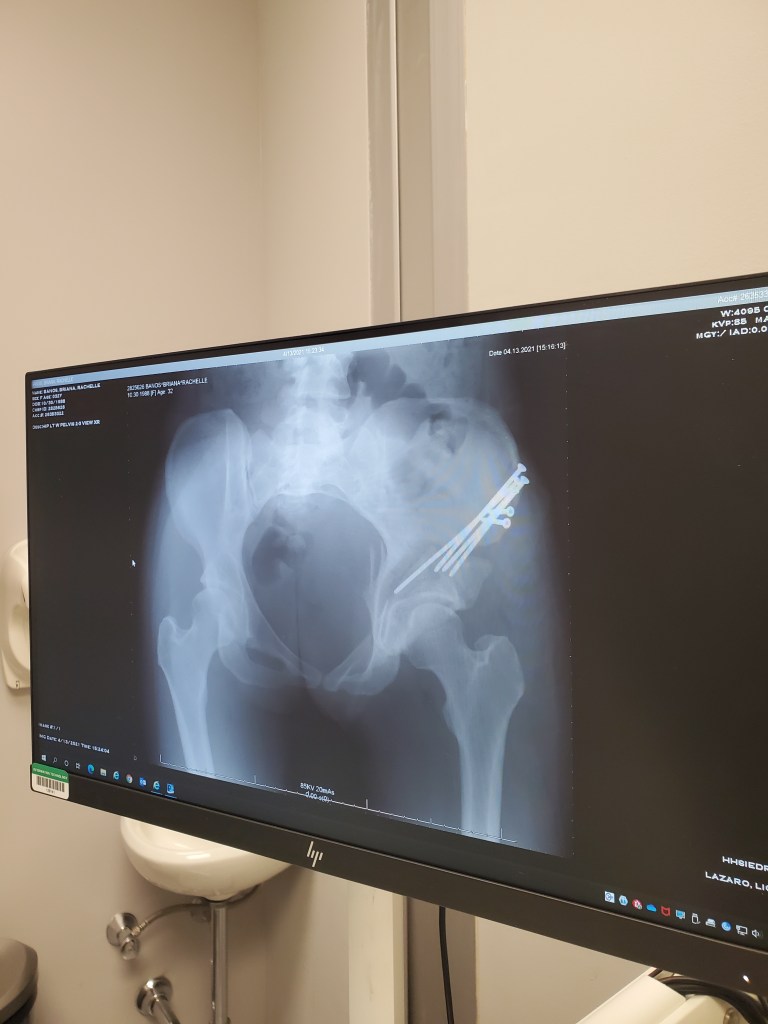

It’s now been 5 weeks since my first arthroscopy surgery and 3 weeks since my PAO surgery.

But let’s cut to the chase… who wants to see the money pics!! Screws and all!